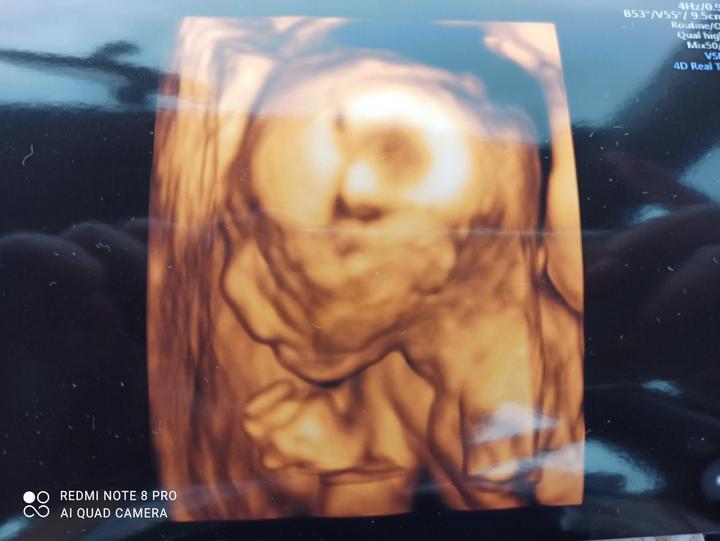

Dnes začínám 3.měsíc třetího těhotenství😁. V úterý odběry a kontrola, jestli ta naše malá larvička roste jak má, takový dlouhý víkend už jsem dlouho neměla. Nic mě nebaví a jsem protivná i sama sobě.